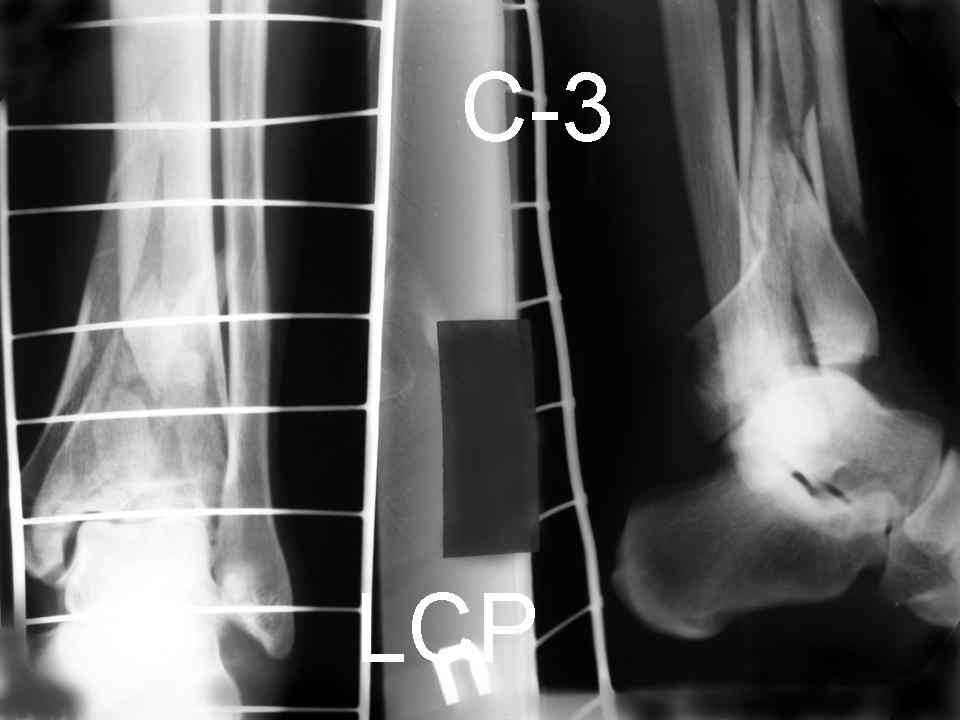

Посылаю результат лечения предыдущего больного через год.

С уважением Дрягин

Кстати, при переломах переднего края по классификации АО В-3 при переломах пилона пластина укладывается по передней поверхности. Она достаточно тонкая и эластичная, не надо этого бояться. Посылаю три снимка.